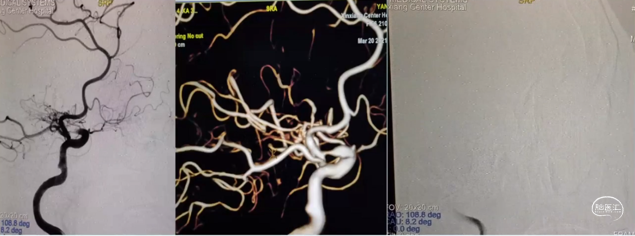

左颈内动脉造影

右颈内正侧位DSA

复查左颈内DSA

手术前后左颈内DSA对比